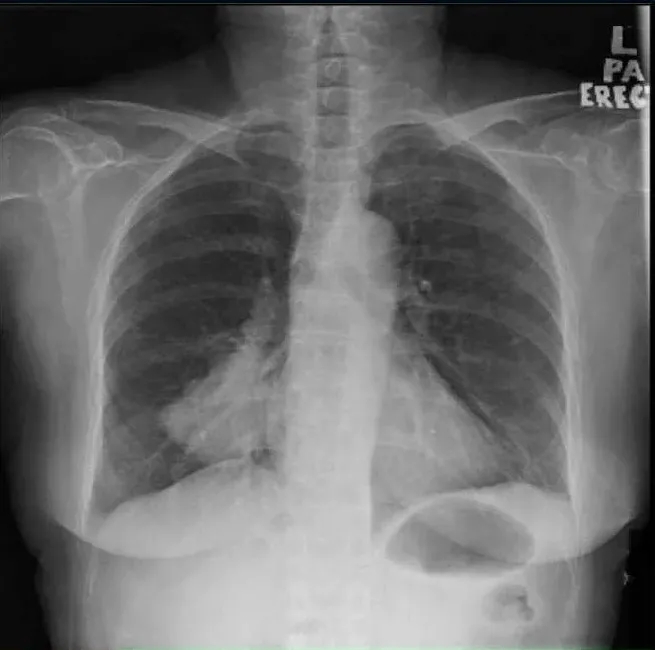

她第一次就诊时的常规胸片(图1)检查偶然发现了右肺肿块。随后的胸部增强计算机断层扫描(CT)(图2)显示肺右下叶后基底段的肺肿块大小为4.7×7.0×7.0 cm(前后×宽度×头尾)。肿块附近也有卫星结节。对肿瘤进行支气管镜活检,组织病理学检查(HPE)结果显示腺癌,证实为原发性肺恶性肿瘤,表皮生长因子受体(EGFR)基因的外显子19缺失。

图2. 胸部计算机断层扫描显示右下叶肿块,周围有卫星结节(箭头)